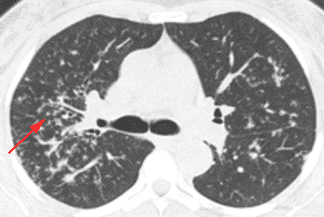

Texto alternativo para a imagem Figuras 1, 2, 3, 4 e 5. Créditos: Dra. Elazir Mota - Rio de Janeiro/RJ

Descrição das figuras 1, 2, 3, 4 e 5: Tomografia computadorizada do tórax com cortes axiais evidenciando pequenos nódulos distribuídos principalmente ao longo dos brônquios e vasos pulmonares (setas vermelhas). Nos cortes coronal e sagital observa-se o predomínio das anormalidades descritas nas regiões superiores e médias, de localização mais central.

• As alterações pulmonares predominam nas regiões centrais e lobos superiores, sendo geralmente bilaterais e simétricas. Predominam os pequenos nódulos sólidos com distribuição perilinfática, ou seja, ao longo dos brônquios, septos interlobulares, vasos pulmonares e regiões subpleurais. Lesões nodulares escavadas e derrame pleural são raros na doença;